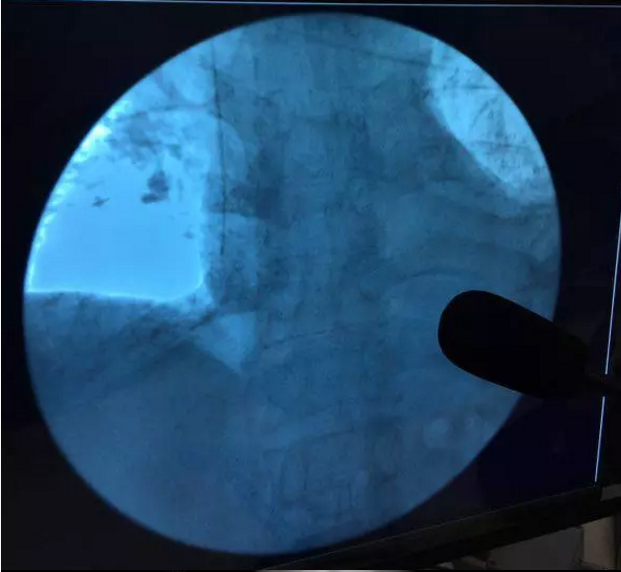

自2017年2月,我院在上级专家老师的指导下,成功为四名癌症患者实施了PICC,之后随着我院派往昆明医科大学第三附属医院学习静脉治疗专科护士的归来,于2017年6月由我院专科护士成功为两名癌症患者实施了PICC,穿刺置管顺利,置管后经胸片显示:导管尖端均在标准位置,患者接受程度良好,标志着我院静脉治疗翻开了全新的一页。